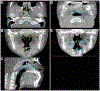

Materials and methods: In this retrospective cohort study, a total of 60 pediatric patients (mean age: 8.00, range: 5-15, 32 females and 28 males) who had tonsillar hypertrophy (size 3 and 4) were included and divided into the control group (n = 20) and expansion group (n = 40). The control group did not undergo any treatment. The expansion group underwent RPE using a conventional Hyrax expander, activated 0.25 mm per day for 4-6 weeks. Final CBCT scans (T2) were performed 13.8 ± 6.5 months after the initial scan (T1). Pediatric sleep questionnaire (PSQ) and BMI were obtained at each timepoint. Volumetric analysis of adenoid and palatine tonsils was performed using a combination of bony and soft tissue landmarks in CBCT scans through Anatomage Invivo 6 imaging software. Paired t-tests were used to evaluate the difference between the initial and final adenoid and tonsil volumes. p values less than 0.05 were considered statistically significant.

Results: Compared to the control group, the expansion group experienced a statistically significant decrease in both adenoid and tonsil volume. There was non-statistically significant increase in volume from T1 to T2 for the control group. For the expansion group, 90.0% and 97.5% of patients experienced significant reduction in adenoid and tonsil volume, respectively. The average volume decrease of adenoids was 16.8% while that of tonsils was 38.5%. The patients had up to 51.6% and 75.4% reduction in adenoid and tonsil size, respectively, following RPE orthodontic treatment. Pearson correlation ranged from 0.88 to 0.99 for each measurement, representing excellent internal consistency. There was a significant reduction in the PSQ scores from 5.81 ± 3.31 to 3.75 ± 2.38 in expansion group (p < 0.001).